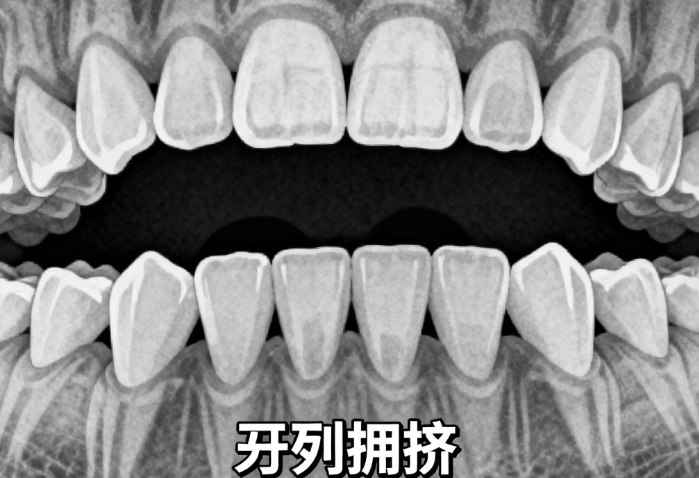

矫正难度直接影响费用,如轻度牙齿拥挤与复杂颌骨发育问题的治疗周期和方案差异,可能导致价格浮动。

适用年龄为6-12岁,处于乳恒牙替换期,具备早期干预条件,如轻中度牙齿拥挤或反颌问题。